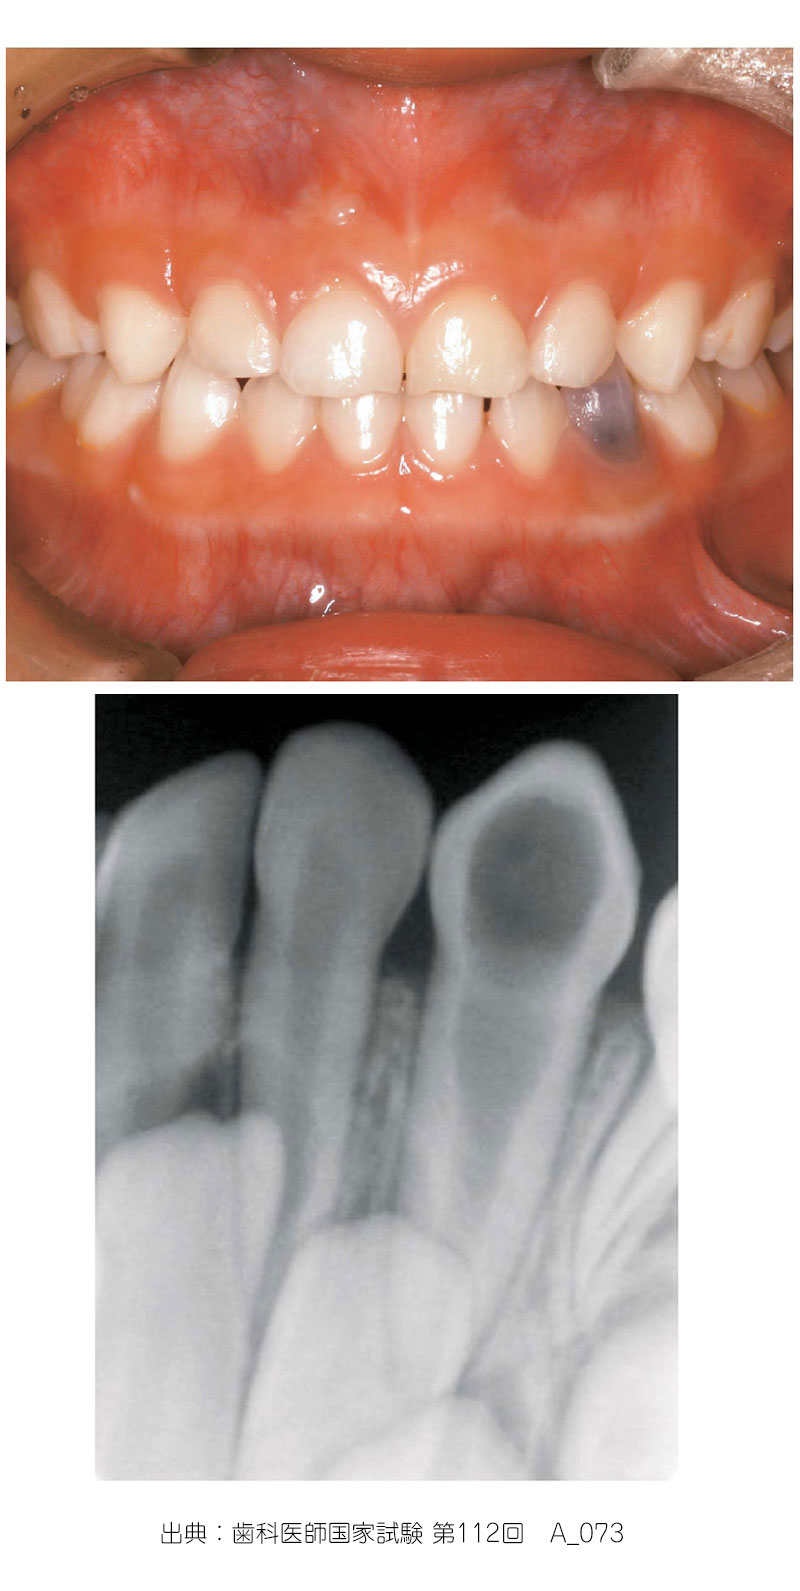

象牙質の歯髄側からの吸収のことをいう

・生活歯髄切断法の予後不良例や外傷の予後観察中にみられることがある

・また、歯冠の一部がピンク色に変化する場合があり(ピンクスポット)、エックス線写真で内部吸収が認められる症例があるが、原因は特定されていない

・不可逆性の慢性歯髄炎による

・歯髄が肉芽性変化をきたすと、肉芽性病変内に破骨細胞が出現し、根管壁が吸収

・好発部位→前歯部

・エックス線→円形吸収像